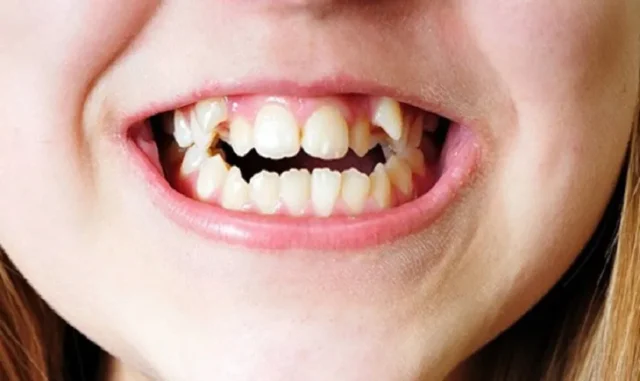

Chỉnh Nha và Bảo Vệ Răng

Nếu răng dài do sai lệch khớp cắn hoặc mòn răng không đều, các phương pháp chỉnh nha như niềng răng có thể giúp điều chỉnh vị trí răng, cải thiện tỷ lệ tổng thể của hàm. Bên cạnh đó, bác sĩ có thể kết hợp các biện pháp bảo vệ như phục hình men răng, dùng máng chống nghiến hoặc hướng dẫn chăm sóc răng miệng đúng cách để ngăn tình trạng tiến triển, giúp duy trì sức khỏe răng lâu dài.